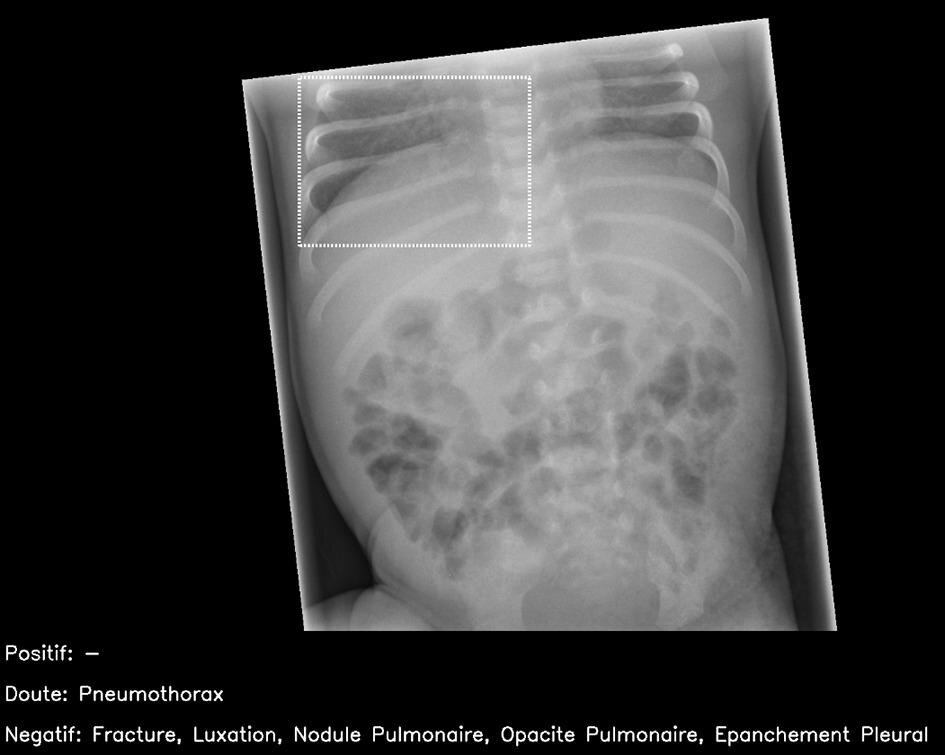

Примеры изображений из теста. Слева: нормальная рентгенограмма брюшной полости, на которой ИИ нашел правосторонний базальный пневмоторакс (ложно положительный результат). Справа: рентген стопы в двух проекциях, на котором виден костно-хрящевой дефект купола таранной кости (пунктирная линия), это нарушение пропустили все врачи и ИИ. Изображения: Susan Cheng Shelmerdine et al., BMJ